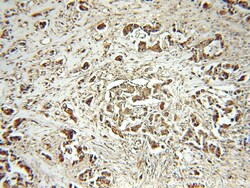

- Submitted by

- Invitrogen Antibodies (provider)

- Main image

- Experimental details

- Immunohistochemistry of paraffin-embedded human liver cancer using 14412-1-AP (PEG10 antibody) at dilution of 1:100 (under 10x lens).

- Submitted by

- Invitrogen Antibodies (provider)

- Main image

- Experimental details

- Immunohistochemistry of paraffin-embedded human breast cancer using 14412-1-AP (PEG10 antibody) at dilution of 1:100 (under 10x lens).